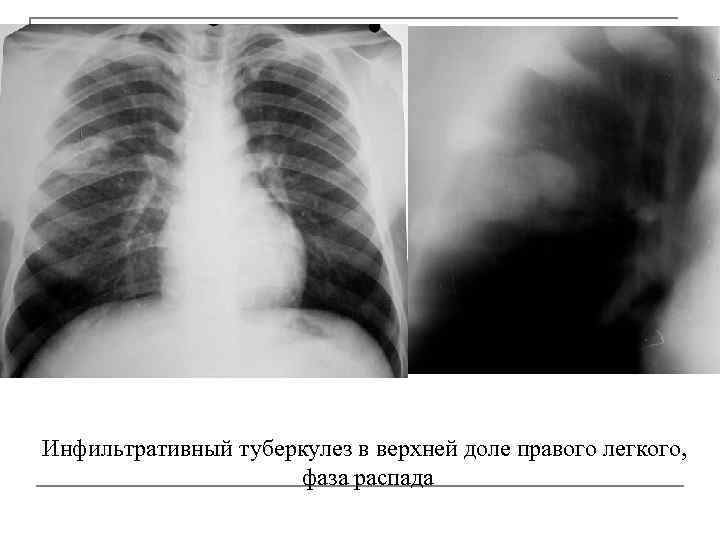

Иллюстрации по теме очагового и инфильтративного туберкулеза

Раздел: Фотодневник открытий